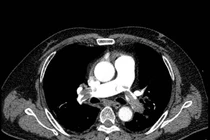

Ông N.V.L (54 tuổi), ở Cần Thơ được chẩn đoán vỡ phình động mạch chủ ngực, tiên lượng tử vong gần như chắc chắn tại một bệnh viện địa phương. Ông được chuyển gấp đến Bệnh viện S.I.S Cần Thơ để tìm kiếm cơ hội sống cuối cùng.

Theo các bác sĩ, Bệnh nhân nhập viện trong tình trạng sốc mất máu, da xanh, niêm nhợt, huyết áp tụt, khó thở… Bệnh viện lập tức kích hoạt báo động đỏ toàn viện, huy động sự phối hợp của các chuyên khoa: Cấp cứu, Gây mê hồi sức, ICU, Can thiệp mạch máu và Phẫu thuật mạch máu. Đây thật sự là một cuộc chạy đua với tử thần, khả năng sống sót chỉ còn 1–2%, bởi động mạch chủ vỡ gây xuất huyết ồ ạt trong lồng ngực, nguy cơ tử vong cực kỳ cao.